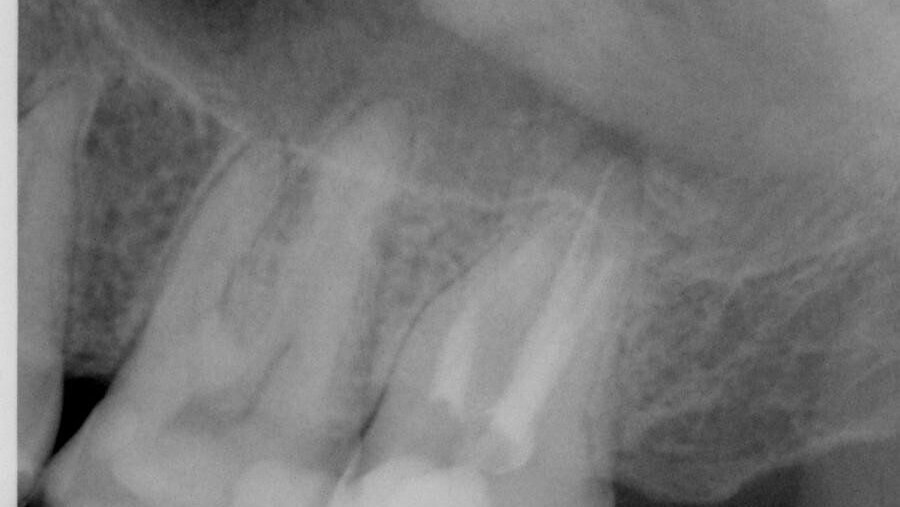

Nonobstant le susdit, l'image fournie rapporte des informations significatives. L'interprétation radiographique de ce film démontre la chose suivante :

1. Il n'y a aucune étanchéité coronaire. Dans la littérature endodontique, la fuite coronaire est fortement corrélée avec l'échec du traitement de canal radiculaire. La dent n'a pas été couronnée, la cavité pulpaire n'a été reconstituée, non plus. Cette apparence radiographique est diagnostique de fuite coronaire. Si on avait eu accès, les canaux montreraient presque certainement l'évidence manifeste d'une telle fuite, manifestée par l'odeur, la gutta-percha décolorée, l'humidité et la purulence possible, parmi d'autres signes. Microbiologiquement, il est pratiquement certain que la preuve d’un biofilm bactérien serait localisée, à côté de la gutta-percha, existante dans les canalicules, cul de sacs et autres secteurs inaccessibles de l'espace du canal radiculaire.

2. Il y a une solution de continuité, dans la préparation et l'obturation de la conicité, de la couronne à l'apex, dans les trois racines. Les moitiés coronaires des disto-vestibulaires (D-V), mésio-vestibulaires (M-V) et les canaux palatins ont une conicité plus grande que les moitiés apicales. Il apparaît que la forme préparée dans les moitiés coronaire a été faite avec des forets Gates Glidden.

Une forme de canal plus prévisible pourrait avoir été préparée utilisant un instrument comme la Twisted File (TF; SybronEndo). Pour cette dent particulière, la TF aurait préparé le canal palatin en, environ, deux à trois insertions à un 0.10/25 après la création d'un chemin de passage. Le M-V et les canaux D-V (et M-V2 si présent) pourrait aussi avoir été préparé à un 0.08/25, en trois à quatre insertions, après la création d'un chemin de passage. Tandis qu'une étude complète du TF est au-delà de la portée de cet article, en utilisant les TF, dans ce cas clinique, on aurait obtenu une conicité optimale, avec relativement peu d'insertions et préservé la structure de racine. On aurait aussi réduit, au minimum, la possibilité de fracture verticale de racine et la perforation latérale. Le degré d'ablation de dentine à l'aspect distal de la racine M-V et l'aspect moyen de la racine D-V indique que la paroi de racine résiduelle est très mince. Tandis qu'il n'apparaît pas qu'une perforation latérale est arrivée, les renseignements radiographiques disponibles sont limités et il n'est pas possible de déterminer s'il y a une perforation. Une telle ablation excessive de dentine est corrélée avec le risque à long terme de la fracture verticale.

3. Il y a une lésion radiographique à l'apex de la racine palatine. Il est inconnu de la vue radiographique, si des lésions supplémentaires sont présentes à l'apex du M-V et les racines du D-V.

4. Il y a des vides d'obturation dans le palatin et la racine M-V. Les espaces de canal radiculaire n'ont pas été remplis tridimensionnellement. De tels vides dans l'obturation (à part d'un manque d’étanchéité coronaire) provoqueraient des questions sur la qualité du nettoyage et de la mise en forme.

5. Bien que, non basée sur une observation radiographique empirique, la longueur de travail du nettoyage, la mise en forme et l'obturation semblent être appropriés comme le fait le diamètre maître apical, mais cela peut n’avoir rien de commun avec la réalité clinique, la vraie longueur de travail idéale et/ou maîtriser le diamètre apical.